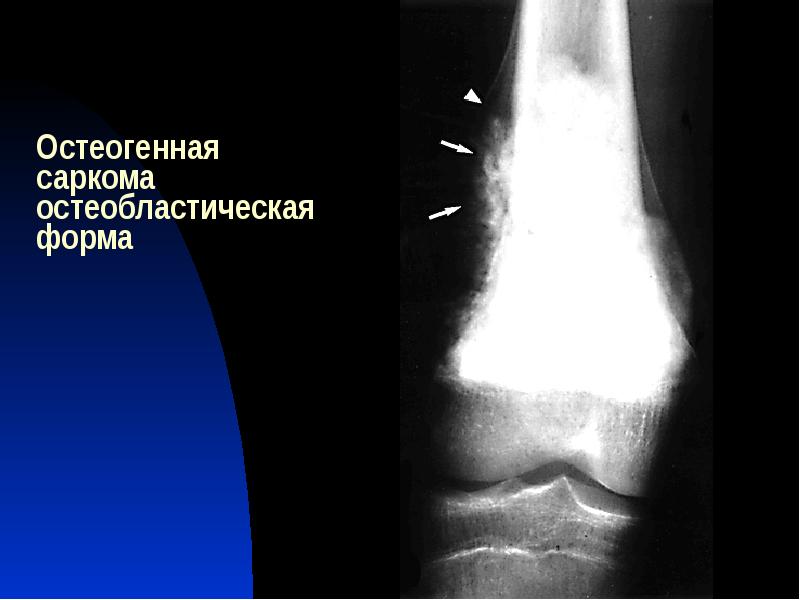

Рентгенологическая картина остеогенной саркомы кости - 98 фото